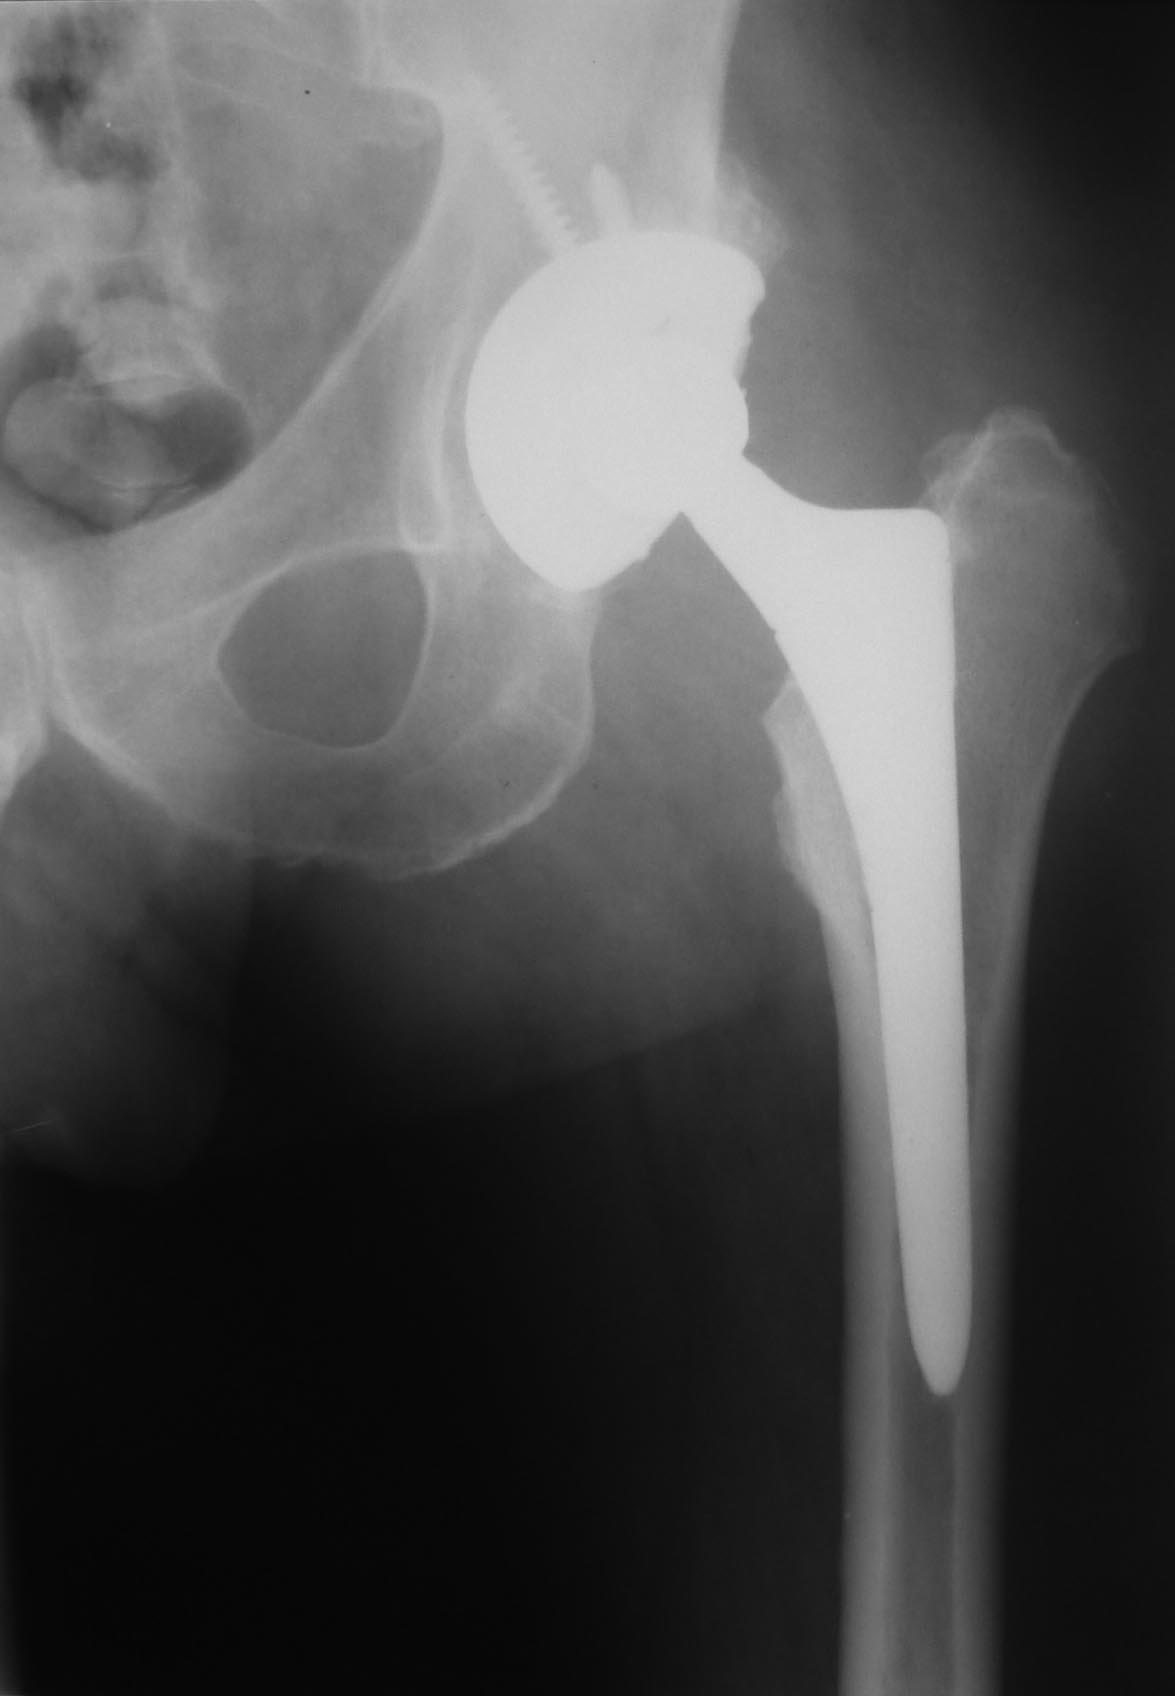

Уважаемые коллеги.Есть ли у кого-нибудь опыт сохранения эндопротеза при

связанном с травмой нагноением без признаков нестабильности протеза и

деструкции костной ткани?

Пациент 55 лет. 6 лет после эндопротезирования по поводу коксартроза. На

майские праздники упал со скамейки на ягодицу. За помощью обратился

только через месяц из-за слегка болезненной припухлости в области

ягодицы на стороне эндопротеза. При пункции под УЗ-контролем удалено

около 200 мл гноеподобной жидкости из области эндопротеза (пункция

выполнена через переднелатеральный доступ). Посев стерильный. Ни разу не

отмечена лихорадка. СОЭ 87, С-рб 67. Жидкость снова набралась за неделю.